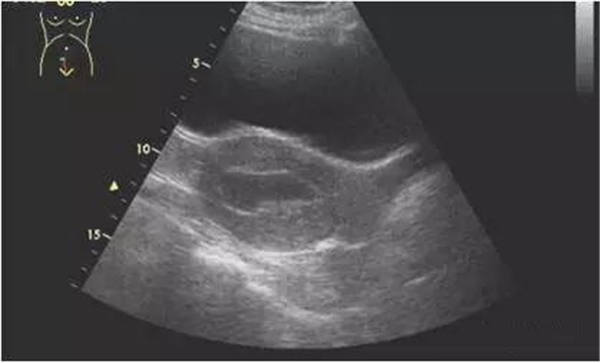

2、宮腔積血、積膿、積液

(宮腔積液)